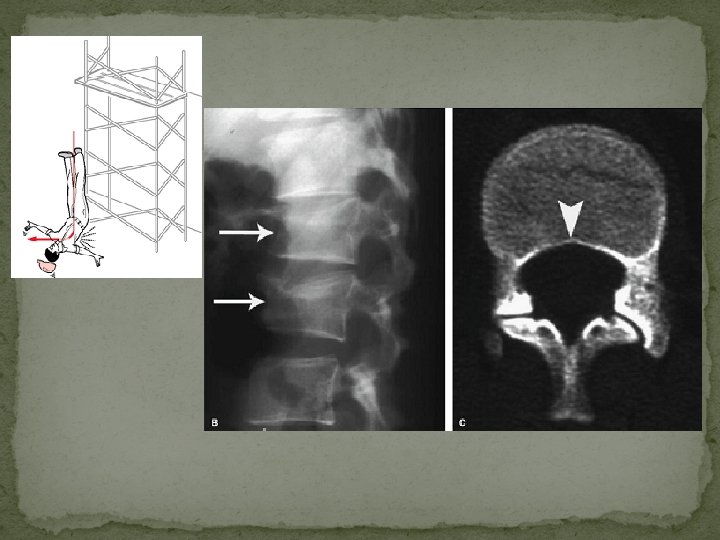

Axial Load Injury (vertical compression) �burst fractures of the thoracolumbar junction and lumbar spine �classically occurs after landing on both feet or buttocks following a fall from a height (lover's fractures when associated with bilateral calcaneal fractures) �Rarely, due to seizure or electrocution

Mechanism – �Axial compression of the vertebral body from above by the nucleus pulposus, which explodes into the superior vertebral endplate to result in centripetal displacement of the body and its fracture fragments �The retropulsion of the posterior aspect of the vertebral body into the spinal canal is pathognomonic of a burst fracture �As the PLL is often intact, spinal traction can reduce this displaced fragment by tightening the PLL

�Posterior bowing of the vertebral body margin is diagnostic of an axial compression (burst) fracture.